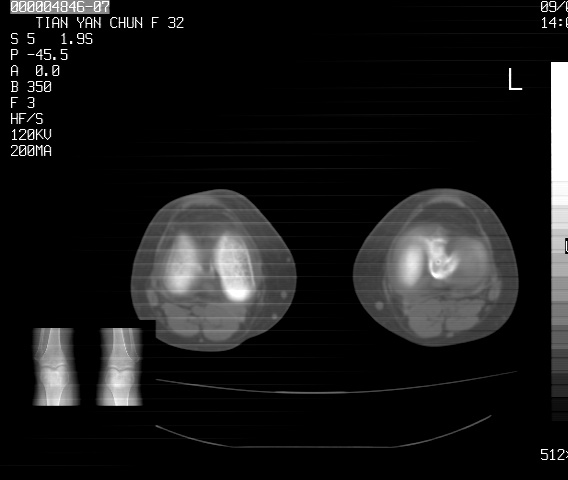

标题: CT18487:请会诊,女32岁,左膝疼痛数日 [打印本页]

标题: CT18487:请会诊,女32岁,左膝疼痛数日

关节面软骨有硬化环考虑退行性变

定位片可见髁间棘骨质增生,支持膝关节退行性变。

定位片可见髁间棘骨质增生,支持膝关节退行性变。建议mri 检查

考虑骨性关节炎